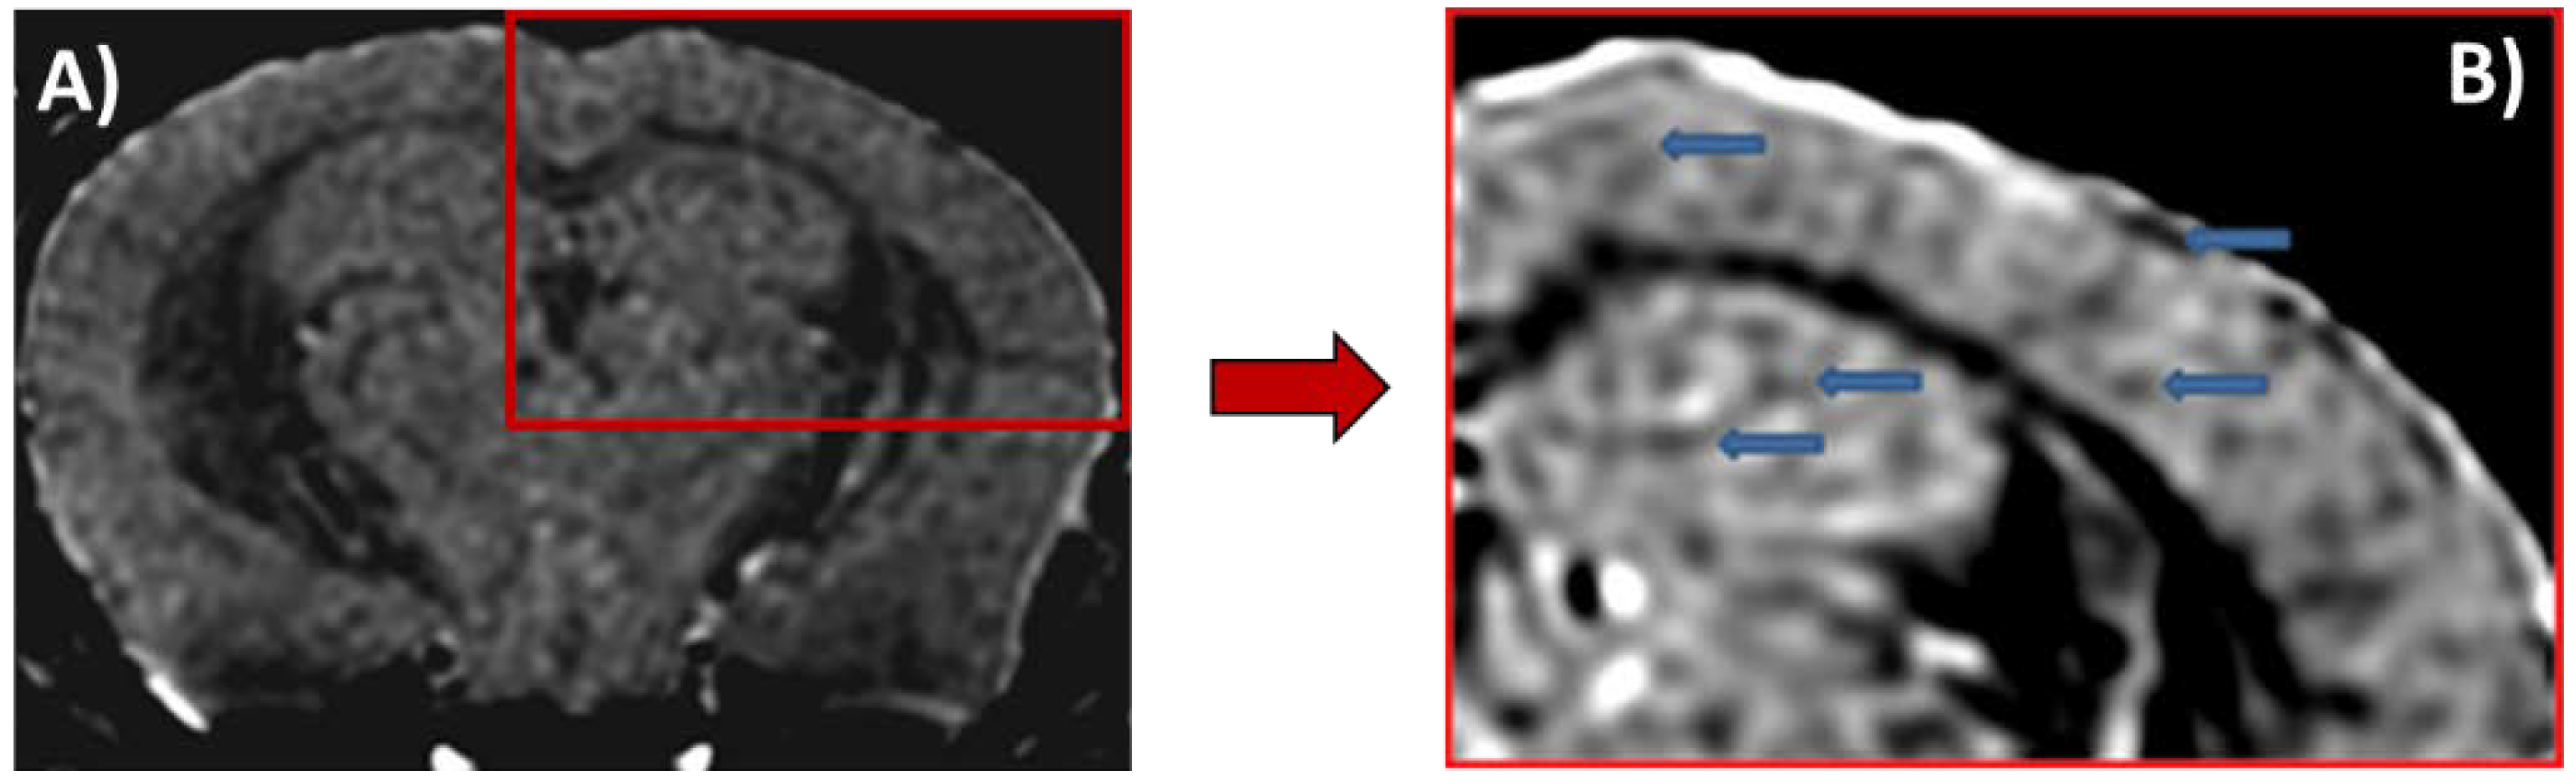

- Wadghiri, Y.Z.; Li, J.; Wang, J.; Hoang, D.M.; Sun, Y.; Xu, H.; Tsui, W.; Li, Y.; Boutajangout, A.; Wang, A.; et al. Detection of amyloid plaques targeted by bifunctional USPIO in Alzheimer’s disease transgenic mice using magnetic resonance microimaging. PLoS ONE 2013, 8, e57097. [Google Scholar] [CrossRef]